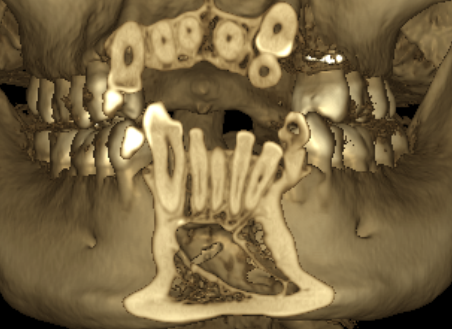

☆本院特別巨資增設 ”千萬級3D AI透視電腦斷層”,並配合“成骨膠原蛋白”施作 (上述兩項目前健保無給付),讓您遠離神經傷害、口鼻竇(炎)相通...等併發症,除健保之外,難免會有避免併發症風險的自費項目,網路上經常會有看到智齒拔完後唇麻、舌麻、口鼻竇相通等併發症,在本院嚴格自我要求下,此類併發症在本院幾乎趨近於零。

(兩條紅線中間黑色區域即為神經管)